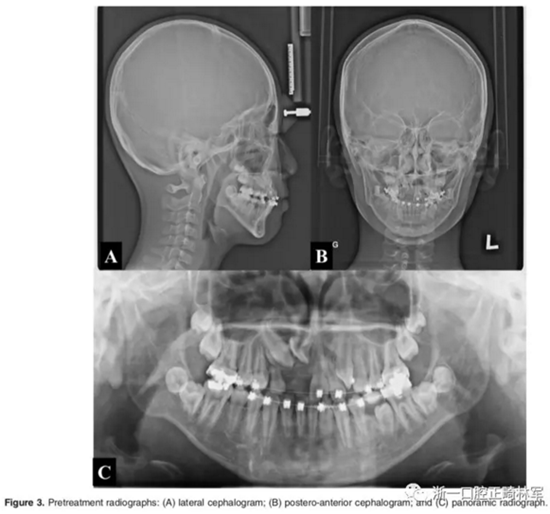

影像檢查:

全景X片及CBCT示:11-13復(fù)雜阻生,上頜前牙區(qū)牙槽骨水平不足;11阻生,遠(yuǎn)中旋轉(zhuǎn)90°,牙冠朝向腭側(cè),根尖位于鼻底、前鼻棘皮質(zhì)骨內(nèi),牙根形態(tài)彎曲;12、13不完全易位,12位置偏腭側(cè),13位置偏舌側(cè),12的牙根形態(tài)也較彎曲。

診斷:骨性I類,牙性II類,高角,多牙阻生,面部不對(duì)稱(右偏),上下切牙直立。